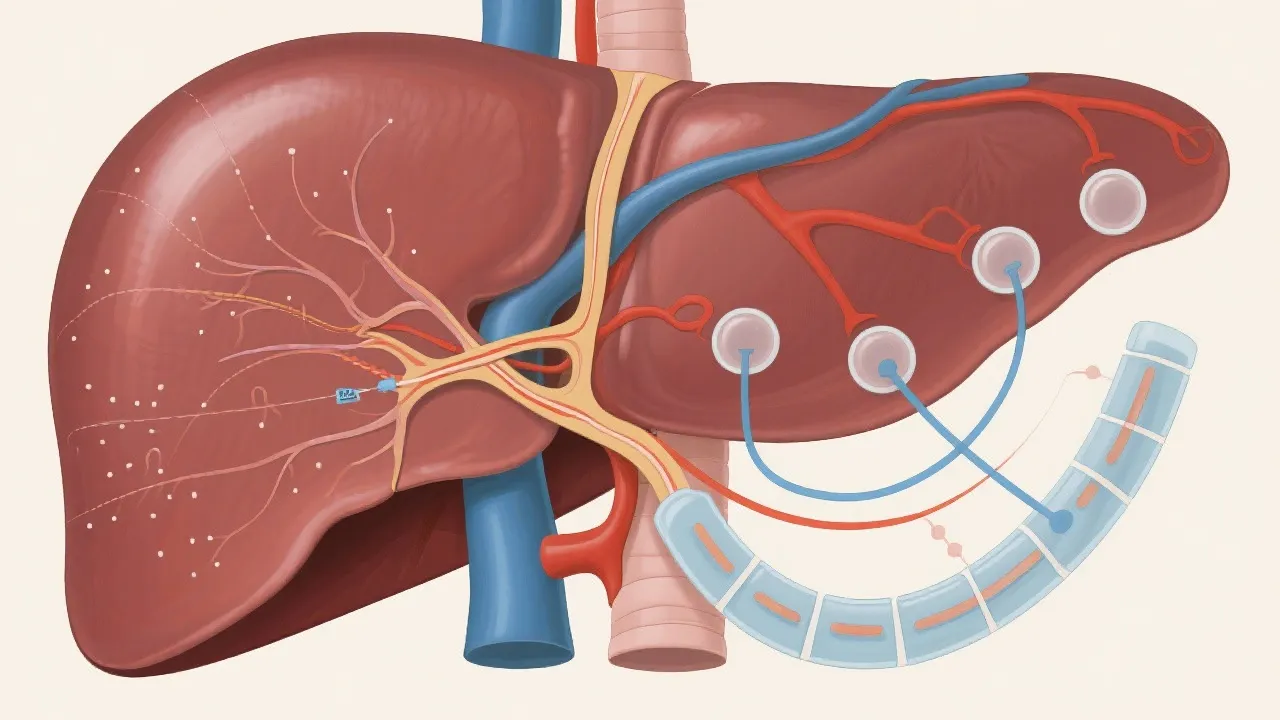

To better grasp how hepatic steatosis develops, it's essential to understand the underlying mechanisms contributing to fat accumulation in the liver. Several factors, including genetic predisposition, metabolic dysregulation, and environmental influences, play significant roles in hepatic steatosis. The liver plays a critical role in metabolic processes, including the synthesis, storage, and breakdown of fatty acids. Key pathways involved in the accumulation of fat in liver cells include an imbalance between lipid uptake and fatty acid oxidation, increased de novo lipogenesis (the process by which the liver converts carbohydrates into fat), and impaired export of very-low-density lipoproteins (VLDLs).

Insulin Resistance: Insulin resistance is one of the primary mechanisms behind the development of hepatic steatosis, particularly in individuals with obesity and type 2 diabetes. When the body becomes resistant to insulin, it impairs the liver's ability to appropriately respond to insulin's signaling, leading to increased fat accumulation within the liver cells.

Inflammation: Chronic low-grade inflammation is also a key player in the progression of hepatic steatosis. Over time, the excessive fat accumulation can lead to cellular stress, triggering inflammatory pathways that can further compound liver damage and contribute to the development of NASH. Understanding these mechanisms can assist in developing targeted treatment interventions.

Understanding the progression of hepatic steatosis can help in awareness and early intervention. Initially, the liver accumulation of fat may not cause any symptoms, often going unnoticed until routine blood tests show elevated liver enzymes. However, over time, persistent fat accumulation can lead to oxidative stress and inflammation. This inflammatory response is crucial in the transition from simple hepatic steatosis to NASH and ultimately to more severe liver conditions like fibrosis or cirrhosis.